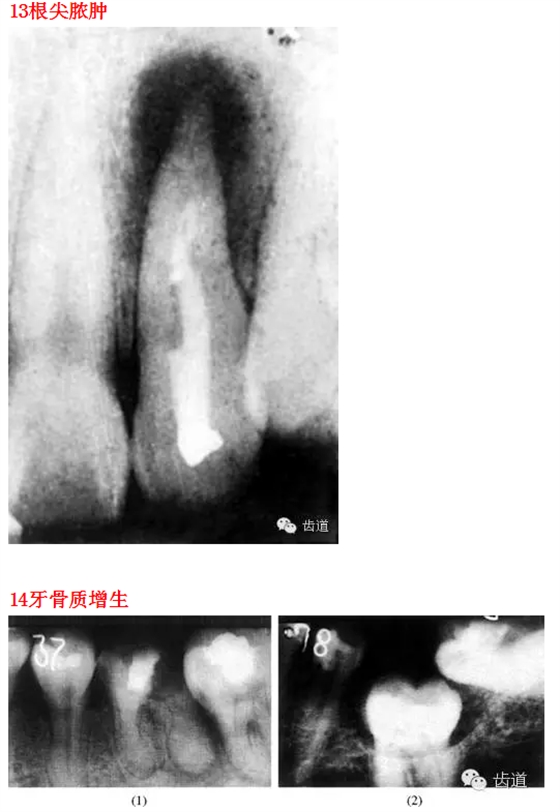

26種口腔病變X光片